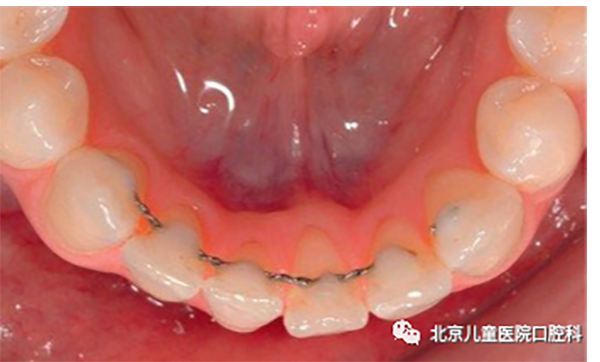

多为粘接于牙齿舌面的舌侧丝保持器。常用于下切牙拥挤解除后需要永久保持的成年患者。

包括下切牙拥挤复发再排齐的活动保持器,及防止骨性错合复发的改良功能保持器。